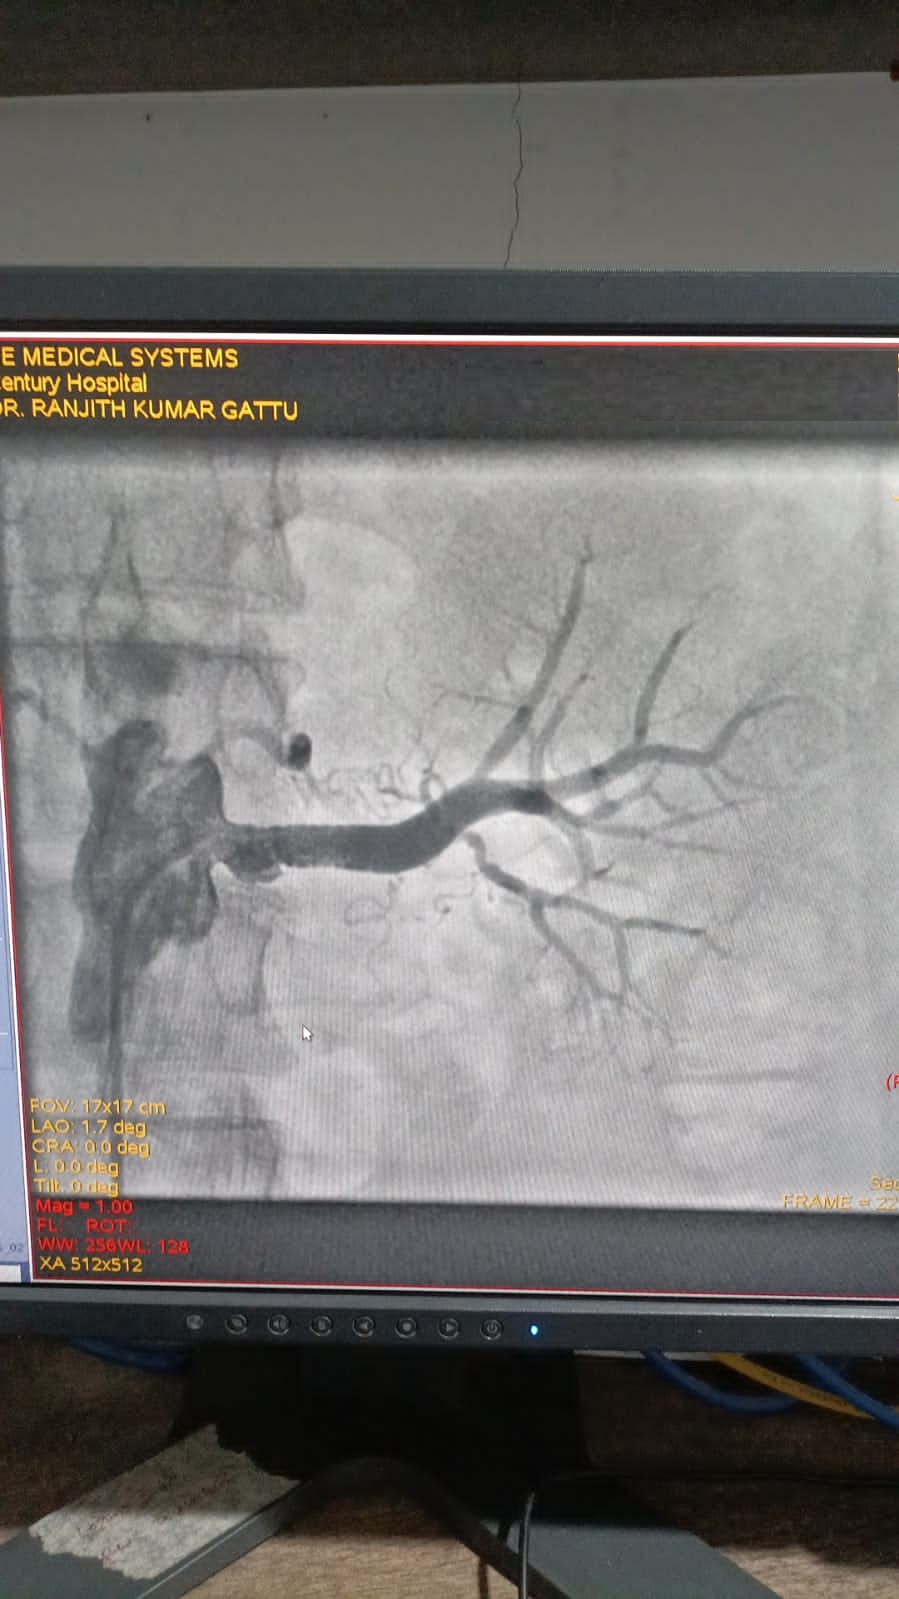

Left Coronary Artery